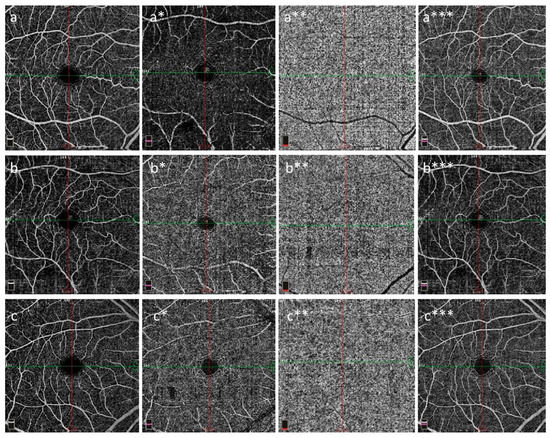

1. Introduction

2. Materials and Methods